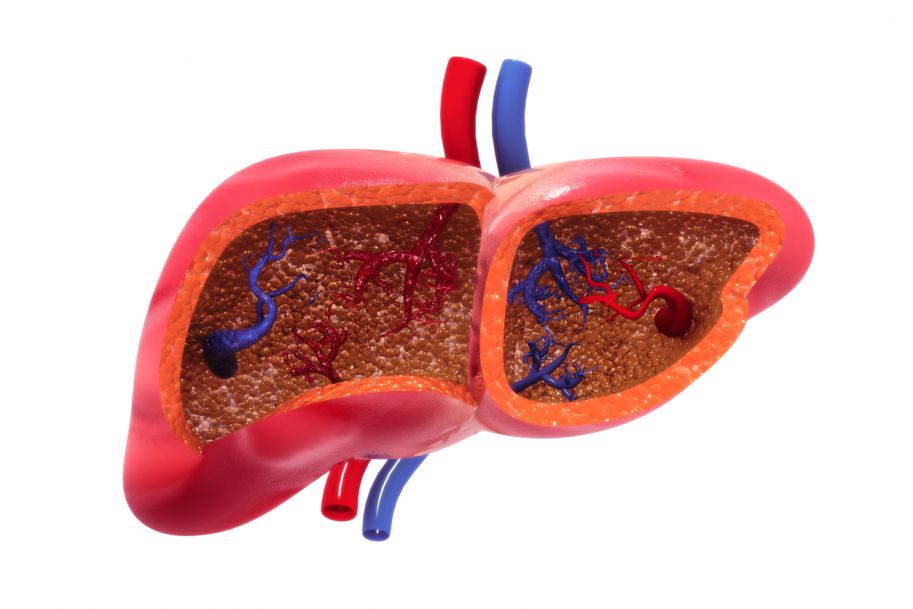

Nowotwory wpływają na czynność wątroby

Nowotwory często uwalniają do krwioobiegu cząsteczki doprowadzające do stanu zapalnego wątroby, powodując gromadzenie się tłuszczu i upośledzając normalne funkcje detoksykacyjne tego narządu.